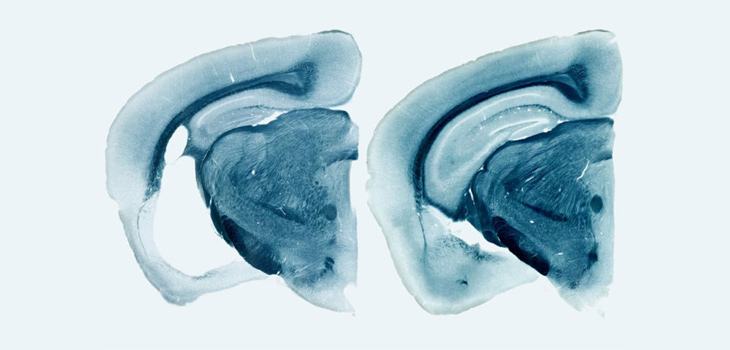

'Oleadas' de actividad neuronal dan nuevas pistas sobre el alzhéimer

Con la falta de consciencia en el sueño profundo la actividad de millones de neuronas viaja por la corteza cerebral. Este fenómeno, conocido como oscilaciones lentas, está relacionado con la consolidación de la memoria. El proyecto europeo llamado <a href="https://anr.fr/en/funded-projects-and-impact/funded-projects/" title="SloW Dyn" alt="SloW Dyn" target="_blank">SloW Dyn</a>, dirigido por científicos españoles, ha permitido descubrir anomalías en esta actividad en ratones con un deterioro similar al alzhéimer.